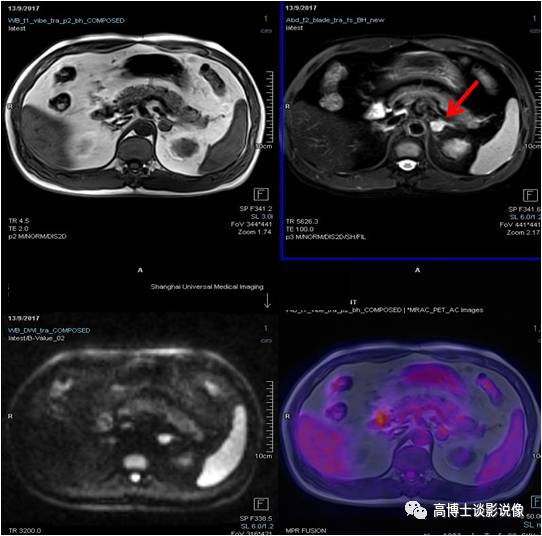

PET/MR

肾上腺

肾上腺腺瘤

中年男性,无任何症状。左侧肾上腺结合部见一长径约1.8cm结节,FDG稍摄取,考虑为肾上腺腺瘤。

点评

根据是否有功能,可分为无功能性和功能性腺瘤。一般来说,偶然发现的肾上腺腺瘤都是无功能性的。对于无功能性腺瘤,注意定期复查。功能性腺瘤需要专科医生进行评估,最好是具备诊断肾上腺肿瘤丰富经验的放射科医师、内分泌医生和外科医生组成的评估小组。

髓样(质)脂肪瘤

中年女性,左侧肾上腺见一大小约1.9cm×2.1cm的类圆形异常信号灶,信号不均匀,内含脂肪信号,考虑为髓样脂肪瘤。

点评:

本病很少出现临床症状,多在体检时偶然发现。如肿瘤较大压迫邻近组织器官或瘤内出血坏死,可引起不适症状。但对于直径较小且无临床症状者应随访观察。